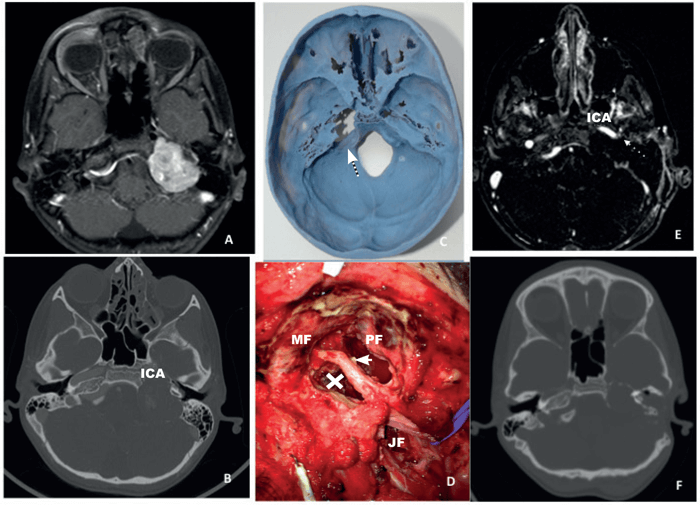

Figure 2. The preoperative MRI (A) and CT (B) of a patient with a left large jugular shwannoma showing the immediate proximity of the tumour to the internal carotid artery (ICA). The preoperatively obtained 3D print showing the precise position of the tumour (C) and a intraoperative picture (first stage procedure) showing the facial nerve (thick arrow) exiting the stylomastoid foramen, remnant of the tumour (X) on the ICA, the jugular foramen (JF), the middle fossa (MF) and the posterior fossa (PF). The final postoperative MRI (E) shows the final outcome with a small remnant of the capsule on the ICA while figure F shows an intermediate postoperative (after the first procedure) CT prior to the facial nerve transposition (case done in two stages).

The 3D-prints (see Figures 1-3) are based on a high-resolution computed tomography (HRCT) scan of the temporal bone and the skull with a thickness of 0.5-0.6 mm (scans performed in various scanners in our department). The patient’s HRCT scan is exported into a 3D software package (Mimics, Materialise, Leuven, Belgium) to convert in to a digital imaging and communications in medicine (DICOM) file to which can be manipulated to reduce and target certain areas. The import of the DICOM file can easily and quickly create accurate 3D models. The software package allows the operator to anatomically analyse and virtually simulate surgery on screen. The final process involved exporting the 3D analysis and the printing of the 3D model. The stereolithographic file was exported to the 3D printer and the printing of model was finalised. We used the printer OBJET 30 (OBJECT 30, Stratasys, MN, United States) and rigid opaque photopolymers (Vero blue) as the printing material for our models; a material that allows detailed printing in blue colour (see Figures 1-3). The time needed for each 3D-model varied between 16 and 22 hours with an approximate cost of £340-£380 for every detailed model for an in-house production. Most of the time is associated with the actual printing, which is usually done overnight.

We primarily use the models for perioperative planning (see Figures 1-3) but also during the consultations to better demonstrate to the patients and their relatives the extent of the disease, the structures involved (internal carotid artery, bulbar nerves, facial nerve, otic capsule, sigmoid sinus and the jugular bulb) and the planned approach. The intraoperative use of the models is typically combined with navigation, when necessary, particularly in revision cases. We also use the 3D prints for teaching and training purposes to explain to our trainees and medical students the complex anatomy of the skull base.

Although the concept of 3D prints has been utilised in a few specialties, in skull base surgery it is still relatively unexplored, representing an emerging concept for teaching, training, planning and executing [2]. Such a concept comes with a very reasonable cost, considering the cost savings that a better-planned surgery has to offer. We found such models very useful for preoperative planning, particularly in revision or two-stage procedures, where the anatomic landmarks have been disrupted by both the pathology and the previous surgical intervention. Additionally, when it comes to a revision case, the skull base print can give, combined with navigation, a very accurate 3D understanding of the precise location of vital anatomical structures (see Figures 1 and 2).